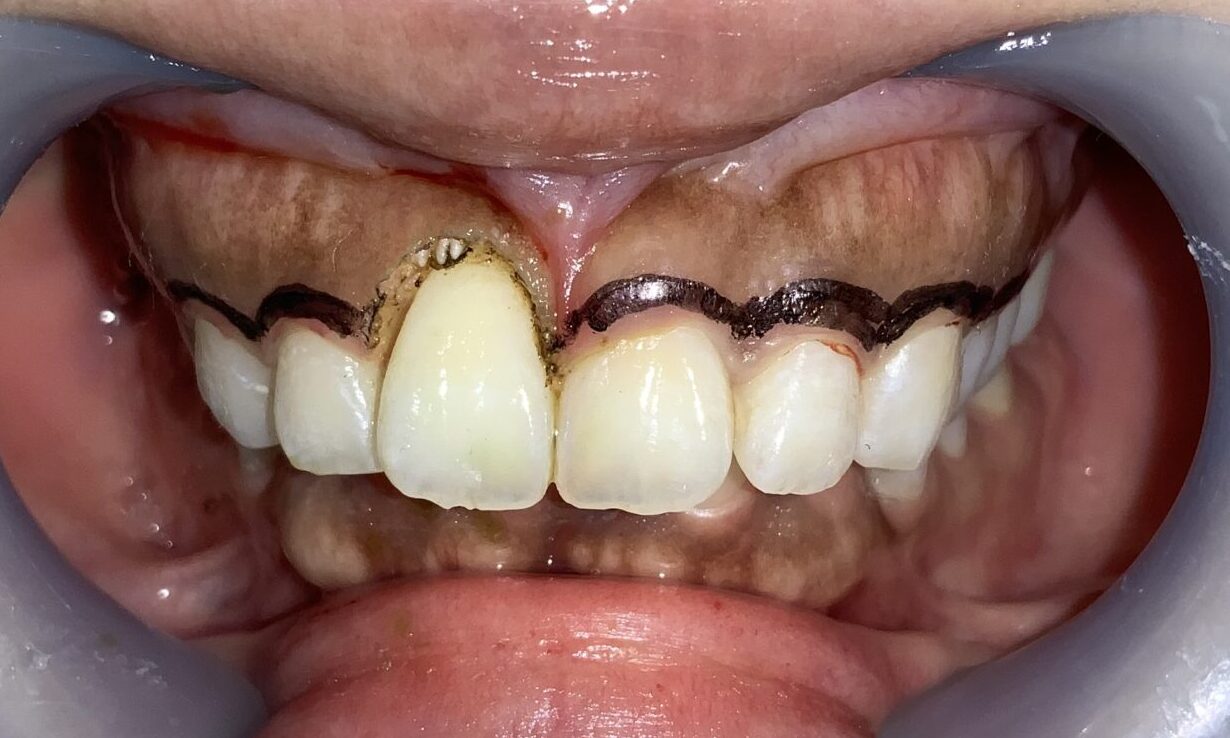

「注意点」

歯槽骨の尖がありますね。

この部分です。この部分は綺麗に整形します。

このように歯槽骨整形も一緒に行なって、綺麗な歯槽骨になったので、後戻りの心配がなくなり、しかも綺麗に仕上がります。

片側だけ終わりました。患者様にも確認をして頂きます。歯ぐきの形、歯の形、笑った時の歯ぐきの見え方を全てご確認頂きました。